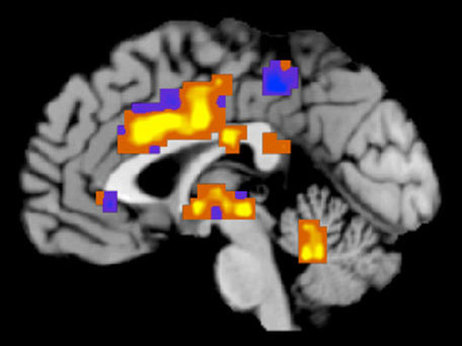

°úÇÐÀÚµéÀº »ç¶÷µéÀÌ ¾î´À Á¤µµÀÇ ÅëÁõÀ» °Þ°í ÀÖ´ÂÁö¸¦ ³ú¸¦ ½ºÄ³´×ÇØ¼­ °è·®ÇÒ ¼ö ÀÖ´Â ¹æ¹ýÀ» °³¹ßÇß´Ù°í º¸°íÇß´Ù.

ȯÀÚ°¡ ¾ó¸¶¸¸Å­ÀÇ ÅëÁõÀ» °Þ°í ÀÖ´ÂÁö, ÀÇ»çµéÀº ȯÀÚ¿¡°Ô ¹°¾îº¸´Â °ÍÀÌ À¯ÀÏÇß´Ù. ±×·±µ¥ ¸¸Èç »ç¶÷µéÀº ÀÚ½ÅÀÇ ÅëÁõÀ» ÀûÀýÈ÷ ¼³¸íÇÒ ¼ö ¾ø°í, ¾î¸°À̳ª ÀÎÁöÀå¾Ö(cognitively impaired)¸¦ °¡Áø »ç¶÷µéÀÇ °æ¿ì´Â ´õ¿í ±×·¯ÇÏ´Ù.

±×·¡¼­, Äݷζ󵵴ëÇÐ ½É¸®ÇÐ/½Å°æ°úÇÐ ºÎ±³¼ö Tor Wager(an associate professor of psychology and neuroscience at the University of Colorado)°¡ À̲ô´Â ¿¬±¸ÆÀÀº ±â´É¼ºÀÚ±â°ø¸í¿µ»óÀåÄ¡(functional magnetic imaging resonance, or fMRI)·Î ³ú¸¦ ÃÔ¿µÇØ ÅëÁõÀ» °´°üÀûÀ¸·Î Æò°¡ÇÒ ¼ö ÀÖ³ª ¿¬±¸Çß°í ±× °á°ú¸¦ New England Journal of Medicine¿¡ ¹ßÇ¥Çß´Ù.

°á·ÐÀº;

ÅëÁõÀ» 90-100% Á¤È®µµ(?)·Î °è·®ÇÒ ¼ö ÀÖ´Ù.

À°Ã¼Àû ÅëÁõ°ú Á¤½ÅÀû/°¨¼ºÀû ÅëÁõÀ» ±¸ºÐÇÒ ¼ö ÀÖ´Ù.

±×·¯³ª ¿¬±¸ÀÚµéÀº µ¿ ¹æ¹ýÀÌ '¾ö»ìŽÁö±â'ó·³ »ç¿ëµÉ °¡´É¼º, ȯÀÚ-ÀÇ»ç °£ ½Å·Ú±¸Ãà ÀúÇØ °¡´É¼º µî ºÎÀÛ¿ëÀ» ¿ì·ÁÇϱ⵵ ÇÑ´Ù.

An fMRI-Based Neurologic Signature of Physical Pain